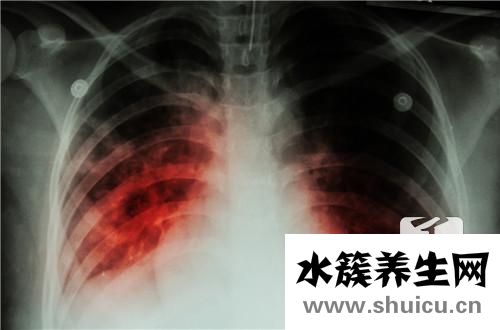

?結(jié)核病是一個普遍的問題,它將對人的身體造成很大的壓力,結(jié)核病的原因很多,通常與病理因素有關(guān),許多人的肺功能本身是正常的,但是由于長期吸入這些非生態(tài) 細菌會產(chǎn)生巨大的肺泡,導(dǎo)致病毒吞噬,并逐漸導(dǎo)致...